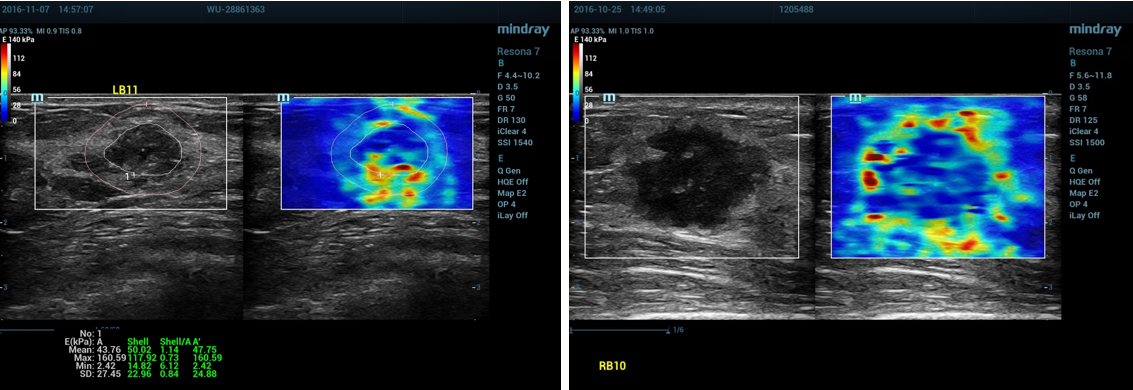

4、正确操作示范:

①乳腺剪切波弹性成像